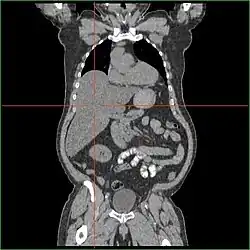

Hepatomegaly

Impairment in the liver's ability to perform gluconeogenesis leads to clinically apparent hepatomegaly. Without this process, the body is unable to liberate glycogen from the liver and convert it into blood glucose, leading to an accumulation of stored glycogen in the liver. Hepatomegaly from the accumulation of stored glycogen in the liver is considered a form of non-alcoholic fatty liver disease. GSD I patients present with a degree of hepatomegaly throughout life, but severity often relates to the consumption of excess dietary carbohydrate. Reductions in the mass of the liver are possible since most patients retain residual hepatic function that allows for the liberation of stored glycogen at a limited rate.

GSD I patients often present with hepatomegaly from the time of birth. In fetal development, maternal glucose transferred to the fetus prevents hypoglycemia, but the storage of glucose as glycogen in the liver leads to hepatomegaly. There is no evidence that this hepatomegaly presents any risk to proper fetal development.

Hepatomegaly in GSD type I generally occurs without sympathetic enlargement of the spleen. GSD Ib patients may present with splenomegaly, but this is connected to the use of filgrastim to treat neutropenia in this subtype, not comorbid hepatomegaly. Hepatomegaly will persist to some degree throughout life, often causing the abdomen to protrude, and in severe cases may be palpable at or below the navel. In GSD-related non-alcoholic fatty liver disease, hepatic function is usually spared, with liver enzymes and bilirubin remaining within the normal range. However, liver function may be affected by other hepatic complications in adulthood, including the development of hepatic adenomas.